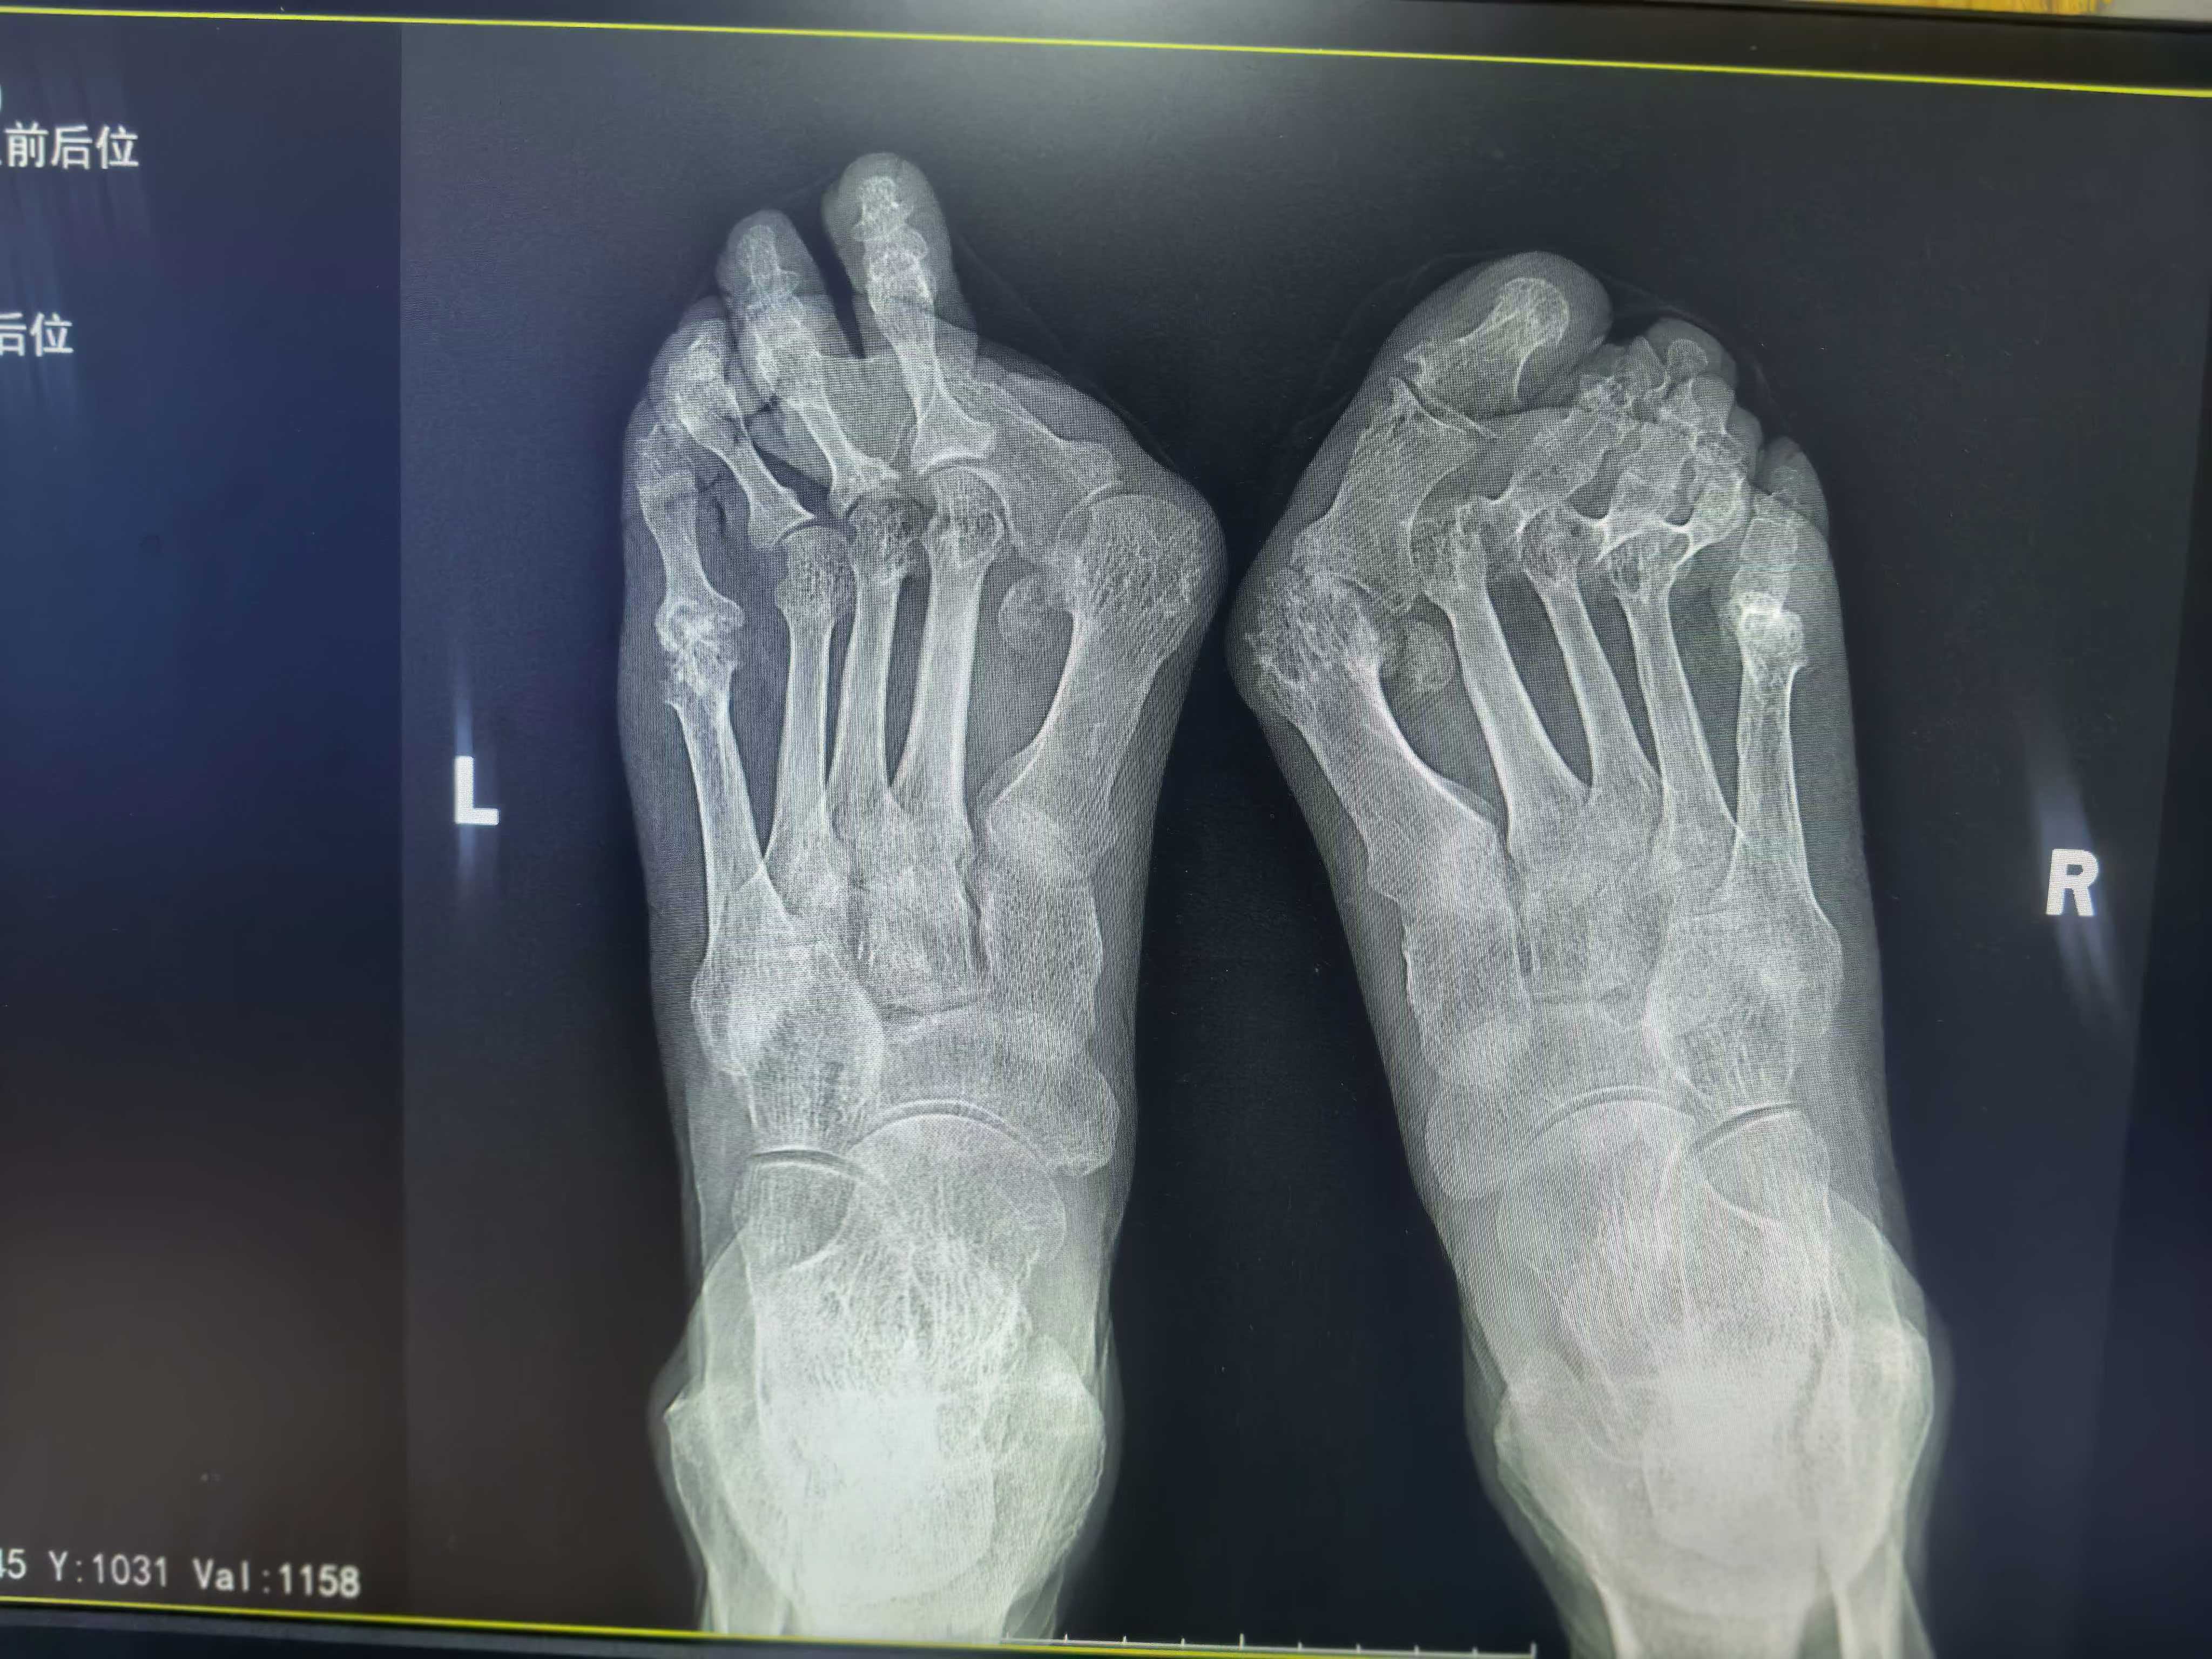

近日,市立医院外一科成功为一名双足重度踇外翻、类风湿关节炎前足畸形的老年男性患者,实施右足跖趾关节成形 + 踇趾关节融合术。该患者因类风湿关节炎长期侵蚀,导致双足足趾严重畸形、踇趾重度外翻,伴随明显疼痛与负重障碍,保守治疗效果不佳,严重影响行走与日常生活,遂来院寻求手术治疗。

面对复杂病情,外一科陈新荣主任带领团队全面查体、精细评估影像学资料。结果显示:患者右足跖趾关节严重破坏、关节间隙消失,伴关节半脱位,保守治疗已无法逆转器质性损伤。

在精准操作下,手术顺利完成。术后复查 X 线片提示:关节融合位置良好,畸形矫正满意。患者疼痛明显缓解,对疗效十分认可。